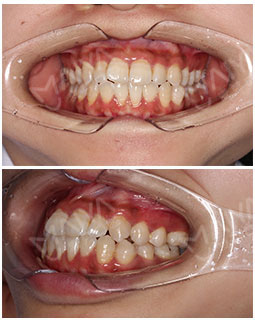

2016年8月8日 到麦芽进行口腔检查

2016年8月8日,经过朋友的劝说,我加入了正畸的行列,我的牙齿上下颌前牙前突咬合不是很好,导致脸型也不是很好看。我对舒适感要求很高,带隐形的完全看不出来。所以选择透明隐形的隐适美。还是私人定制款,嘻嘻。今天来记录我的矫正经历,跟大家一起分享一下,同时给自己留个回忆。我之前就和这边的医生预约好,我很准时的来医院。先是给我拍牙齿的片子,牙齿牙列不齐,幻想着矫牙后的模样~ 相信麦芽的技术!